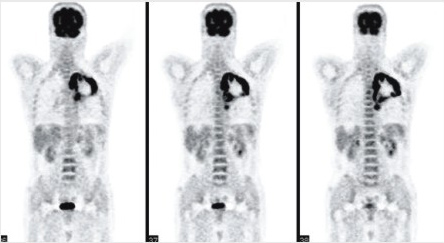

二、PET-CT在腫瘤放射治療中的應用

PET-CT是一種新型發展迅速的能檢測腫瘤和正常組織代謝差異的功能性影像學技術,可以被應用于腫瘤診斷、治療和隨訪等整個臨床過程。由于腫瘤放射治療需要借助于醫學影像進行腫瘤定位,計劃的設計和實施等,而PET-CT又能提供反映腫瘤代謝等生物學信息,這有可能提供一個紐帶將放射治療手段的方法這一物理技術與其所需要解決腫瘤臨床的生物問題關聯起來,從而有望進一步提高腫瘤放射治療效果。

其意義包括兩個方面:1)提高臨床分期準確性:根據PET-CT所提供的信息有利于提高患者治療前的臨床分期準確性,從而有利于臨床上為患者制定出正確的治療總體策略。如資料顯示,應用PET-CT后,能使30-40%頭頸、肺部腫瘤治療策略需要做相應調整,避免患者過度或不足的治療。2)提高了放射治療范圍的準確性:臨床上若希望提高放療療效,首先需要精確確立腫瘤侵犯和累及部位和所需要照射的腫瘤范圍。CT,MRI和B超等影像學手段,固然對一些腫瘤從某些程度上顯示了腫瘤范圍,但離精確放療的靶區精確設置要求相差甚遠。PET-CT有利于發現潛在的遠處轉移腫瘤病灶、相應淋巴引流區域有無淋巴結轉移、區別術后改變中有無腫瘤病灶、伴有肺不張或阻塞性炎癥時的腫瘤范圍的確定和用于定量顯示活動器官中腫瘤大小等問題。